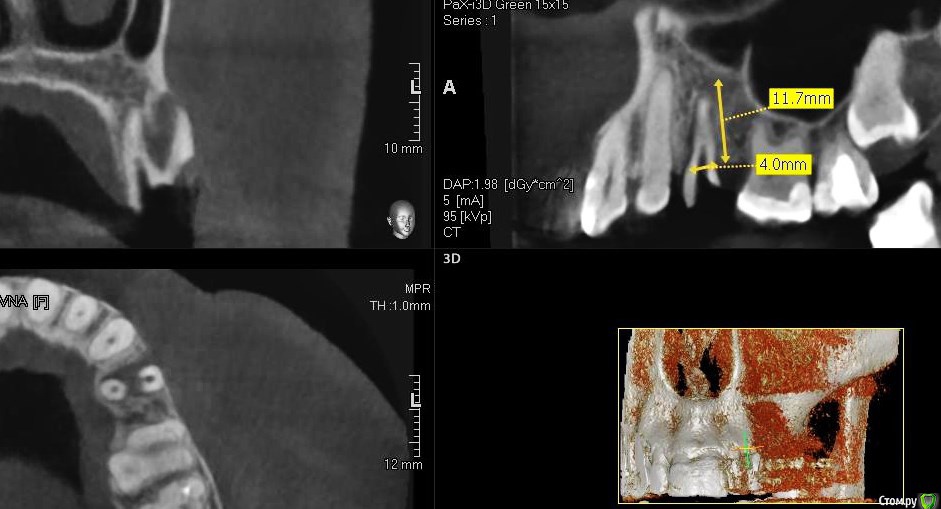

колесников Опубликовано 25 февраля, 2017 Поделиться Опубликовано 25 февраля, 2017 Здравствуйте коллеги! Представляю вашему вниманию этот клинический случай.В ноябре 2016 обратилась пациентка с жалобами на выпадение ортопедической конструкции в обл 24. Объективно: корни 24 не состоятельны. ,на десневом крае в проекции 24 свищевой ход с гнойным отделяемым.На КТ резорбция вестибулярной компактной пластинки и деструкция костной ткани в области щёчного корня.Приняв во внимание крайне негативное отношение пациентки к каким бы то ни было хирургическим вмешательствам и высоким эстетическим требованиям,было решено пойти на немедленную имплантацию .Снимки в день вмешательства,через 7,14 дней и 3мес.Имплант Astra tech profile 4.5х11мм. Сст с бугра вестибулярно. Вместо графта губки Коллапола (не вспомню причину,либо не было в наличии,либо отказ пациента). 15 Ссылка на комментарий

колесников Опубликовано 12 июня, 2017 Автор Поделиться Опубликовано 12 июня, 2017 Контрольное кт спустя 3 мес. Откуда-то наросло 2мм у шейки. Ссылка на комментарий

Doctor Vlad Опубликовано 13 июня, 2017 Поделиться Опубликовано 13 июня, 2017 Откуда-то наросло 2мм у шейки. да видимо графт был, причем не коллапон коллагеновый а костная стружка, даже по первым снимкам после операции там чтото рыхлое торчит. Ссылка на комментарий